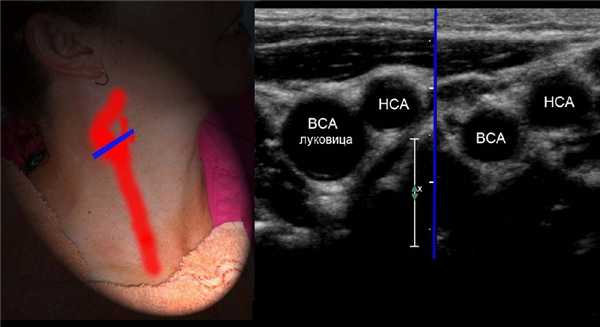

У основания шеи кнутри от ОСА щитовидная железа, кнаружи — внутренняя яремная вена. Под давлением датчика ВЯВ сжимается, а ОСА нет.

От основания шеи перемещайте датчик вверх к бифуркации ОСА — место деления на НСА и ВСА. Здесь небольшое расширение — луковица.

У бифуркации ОСА расширение луковицы, начинается голый ствол ВСА и ветвящаяся НСА. Первая ветвь НСА — верхняя щитовидная артерия.

На уровне бифуркации ВСА шире НСА; расположена кнаружи и кзади от НСА, выше перемещается кнутри; не имеет ветвей на шее.